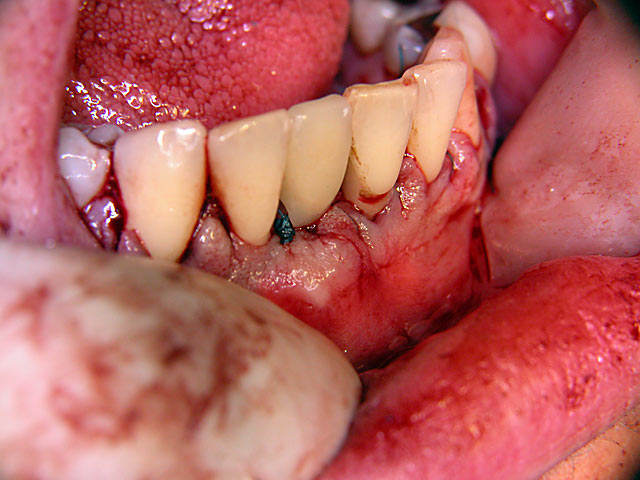

Implantation – Patientenbeispiel 1: